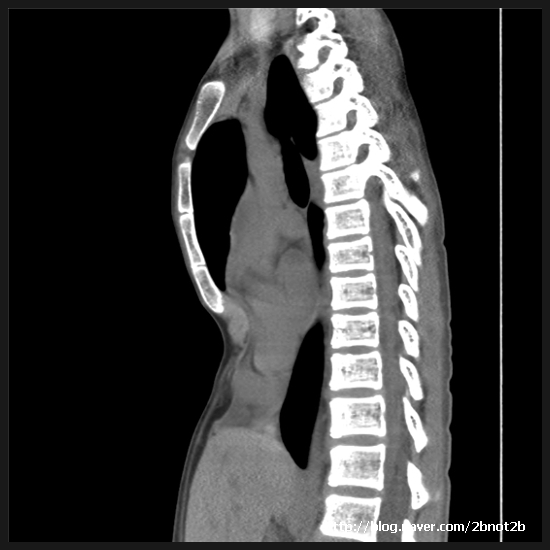

From blog.naver.com

Chest computed tomography scan a Funnel chest (Haller index, 9.9).b Can Funnel Chest Correct Itself learn about pectus excavatum, a chest wall deformity that affects children, and how it can be corrected with a minimally. learn how to do pushups, chest fly, dumbbell row, and other exercises to strengthen. funnel chest can cause a child’s ribs and breastbone to grow inward giving the chest a sunken appearance. pectus excavatum is a. Can Funnel Chest Correct Itself.

(A) Lateral chest roentgenogram shows the severe funnel chest (arrow Can Funnel Chest Correct Itself learn about pectus excavatum, a chest wall deformity in which the breastbone and ribs grow inward, causing a depression in the middle. learn about the causes, symptoms, and treatments of pectus excavatum, a chest wall deformity that can affect heart and. learn about pectus excavatum, a chest wall deformity that affects children, and how it can be. Can Funnel Chest Correct Itself.